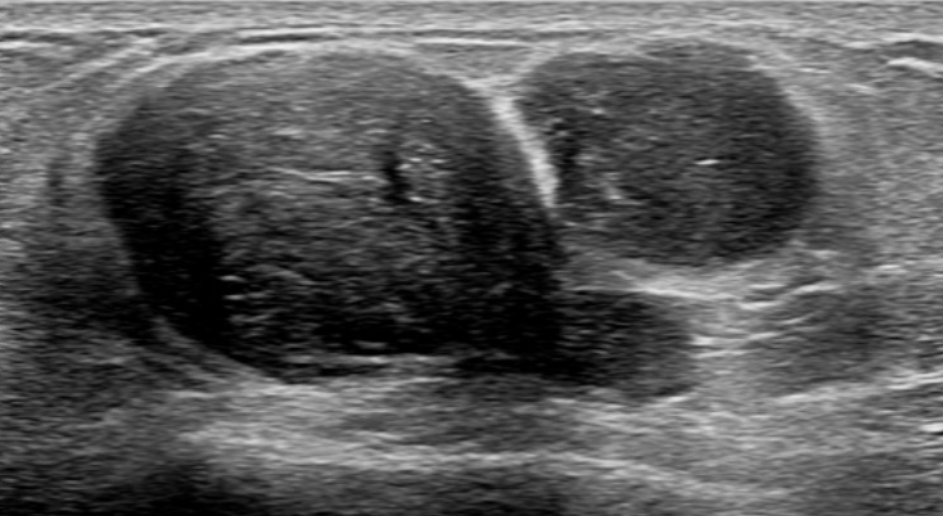

これが葉状腫瘍の厄介な点です。画像検査(マンモグラフィやエコー)や、針を刺して細胞を採る検査(針生検)を行っても、よくある良性のしこり「線維腺腫」と区別がつかないことがあります。

- エコー検査で、しこりの中に「裂け目」や「水たまり(嚢胞)」のような影が見える。